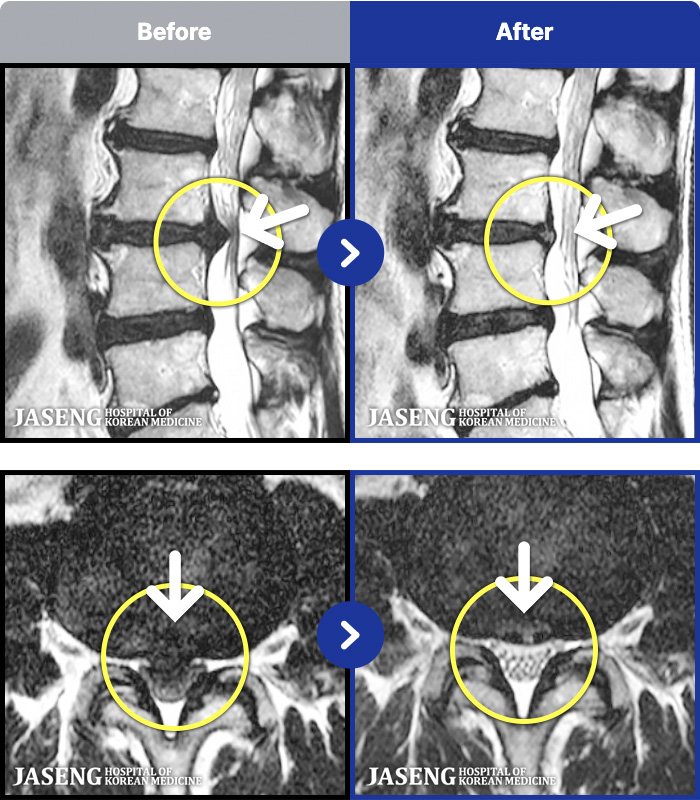

1,241 MRI ũ ʸ Ȯϼ.

MRI ġ

㸮, ٸ ٷ

ǿ

ȯ